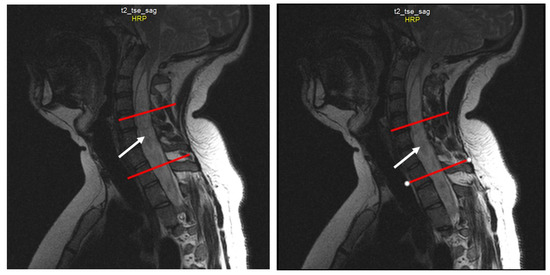

Chiari 1 Malformation (CM1) is classically defined as a caudal displacement of the cerebellar tonsils through the foramen magnum into the spinal cord. Modern imaging techniques and experimental studies disclose a different etiology for the development of CM1, but the main etiology factor [...] Read more.

Chiari 1 Malformation (CM1) is classically defined as a caudal displacement of the cerebellar tonsils through the foramen magnum into the spinal cord. Modern imaging techniques and experimental studies disclose a different etiology for the development of CM1, but the main etiology factor is a structural defect in the skull as a deformity or partial reduction, which push down the lower part of the brain and cause the cerebellum to compress into the spinal canal. CM1 is classified as a rare disease. CM1 can present with a wide variety of symptoms, also non-specific, with consequent controversies on diagnosis and surgical decision-making, particularly in asymptomatic or minimally symptomatic. Other disorders, such as syringomyelia (Syr), hydrocephalus, and craniocervical instability can be associated at the time of the diagnosis or appear secondarily. Therefore, CM1-related Syr is defined as a single or multiple fluid-filled cavities within the spinal cord and/or the bulb. A rare CM1-related disorder is syndrome of lateral amyotrophic sclerosis (ALS mimic syndrome). We present a unique clinical case of ALS mimic syndrome in a young man with CM1 and a huge singular syringomyelic cyst with a length from segment C2 to Th12. At the same time, the clinical picture showed upper hypotonic-atrophic paraparesis in the absence of motor disorders in the lower extremities. Interestingly, this patient did not have a disorder of superficial and deep types of sensitivity. This made it difficult to diagnose CM1. For a long time, the patient’s symptoms were regarded as a manifestation of ALS, as an independent neurological disease, and not as a related disorder of CM1. Surgical treatment for CM1 was not effective, but it allowed to stabilize the course of CM1-related ALS mimic syndrome over the next two years. Full article